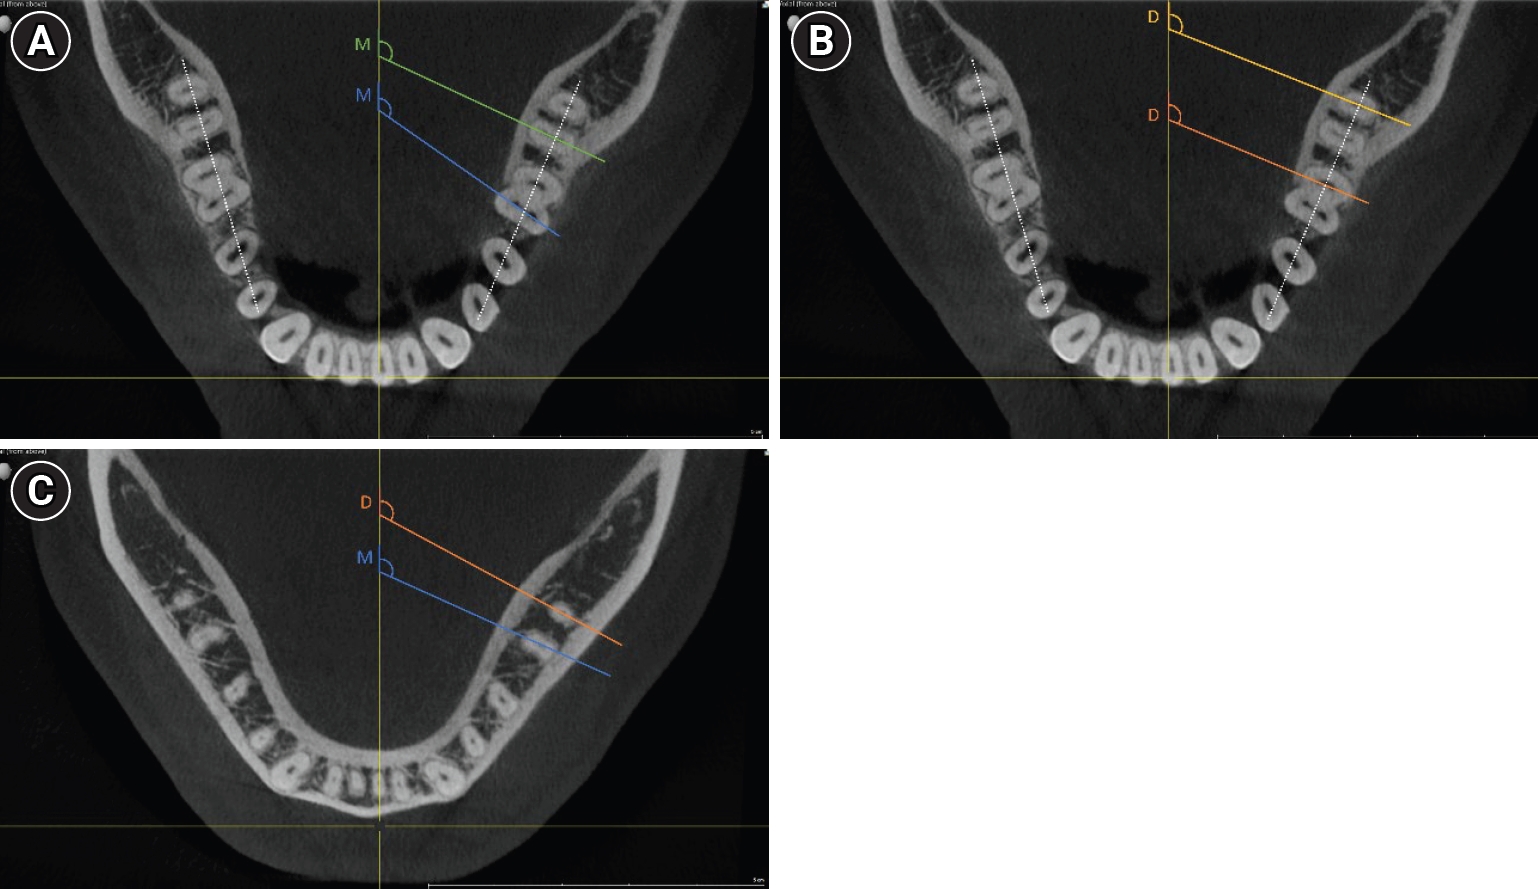

All measurements were performed by a single investigator using the open-source software ImageJ (version 1.54f, open-source; National Institutes of Health, Bethesda, MD, USA), utilizing the central axis as a standardized reference point (Figure 1). The angle at which the individual root canals located buccally would overlap with the lingual root canal was measured for each tooth, starting from the central axis of the jaw. In roots presenting a single oval-shaped canal, the angle was measured along the axis of this anatomical structure. The aim of the study was to investigate the possible superimposition in 2D intraoral radiographs, which are normally taken parallel to the jaw and not placed centrically; therefore, the angle between the jaw and the central axis was additionally measured, and the respective angles were calculated accordingly.

Figure 1.

Examples of the cone-beam computed tomography measurements. Examples of measurements indicative of the angles at which root canals overlap. The measurement lines are colored for better visibility showing either mesial (M) or distal (D) canal pair measurements. In roots presenting a single oval-shaped canal, the angle was measured along the axis of this anatomical structure. The dotted line represents the mandibular arch, and the angle between this reference and the X-ray central axis was also measured for final angle calculations. (A) Mesial canal pairs (mesiobuccal–mesiolingual), coronal level. (B) Distal canal pairs (distobuccal–distolingual), coronal level. (C) Mesial and distal measurements, apical level.